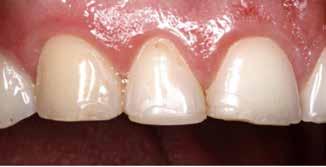

Klinisk undersøgelse viste emaljehypoplasier og hypomineralisering på 1+, +1, 2-, 1-, -1 og -2 (Fig.1). Hun havde Angle klasse II, pladsmangel i begge kæber og agenesi af -5. Der var isninger ved spisning og tandbørstning. Fundene var forenelige